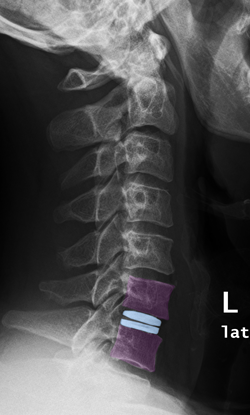

Πρόσθια αυχενική δισκεκτομή και τοποθέτηση τεχνητού αυχενικού δίσκου (μπλέ) Α6-Α7. |